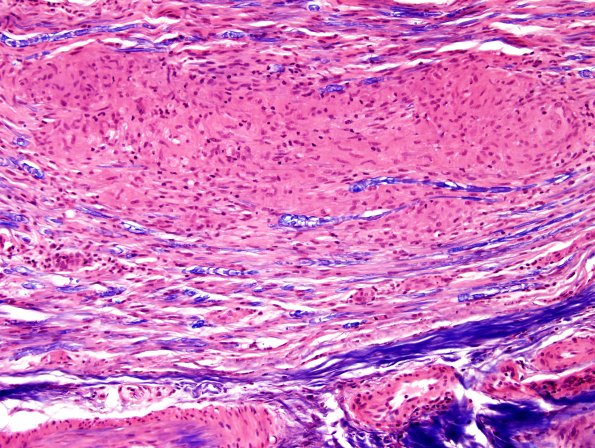

Additional longitudinal sections show axon loss and multiple granulomas. (H&E-LFB)